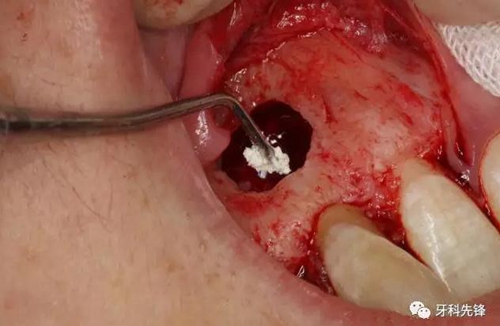

圖14.摘除后的囊腫情況,并用超聲骨刀清理根尖區(qū)后,可清晰看到12牙根未發(fā)育,根管粗大開放。

圖15.開放的根尖區(qū)用MTA封閉。

圖16.調(diào)板好的MTA,輸送至預備好的12根尖區(qū)域。